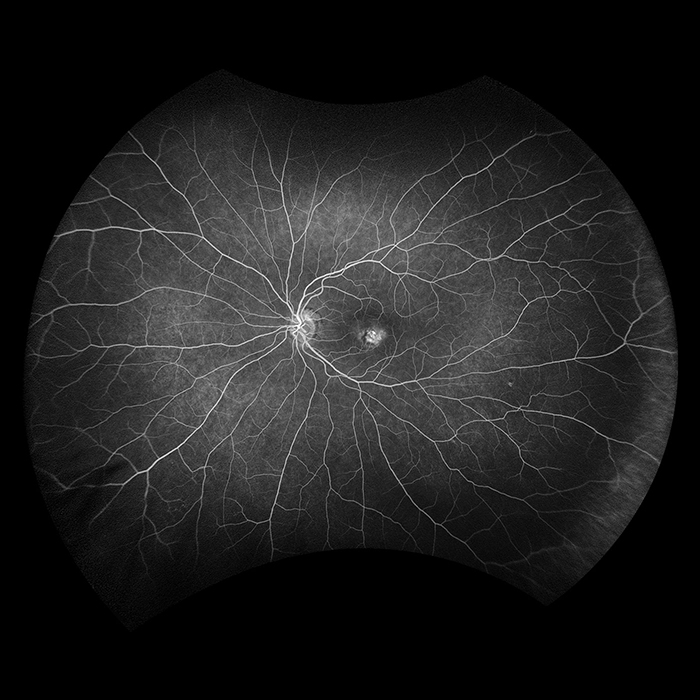

California was developed for medical imaging and is a standard for retinal screening programs. California is available in multiple models with multiple imaging modality options. California produces a 200°, single shot retinal image of unrivaled clarity in less than ½ second and is changing the management of diseases including Geographic Atrophy, Diabetic Retinopathy, AMD, and Uveitis.

Why California?

California was developed to facilitate comprehensive eye exams, document findings, and assist eyecare professionals in disease management and treatment. California is available in various device configurations and image modality options for the flexibility to meet the needs and budget of every eyecare practice. Imaging modalities and viewing options are detailed below.

optomap Image Modalities

- color rgb (available with rg,af,fa combined model)

- color rg

- Sensory Retina

- Choroidal

- green af

- blue af

- fa

- icg